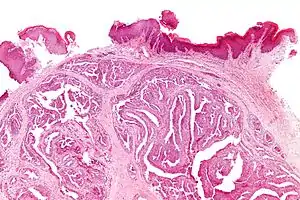

| Micrograph of a papillary hidradenoma with the characteristic papillary structures and epithelium with apocrine snouts. A fragmented overlying epidermis is seen at the top of the image. H&E stain. | |